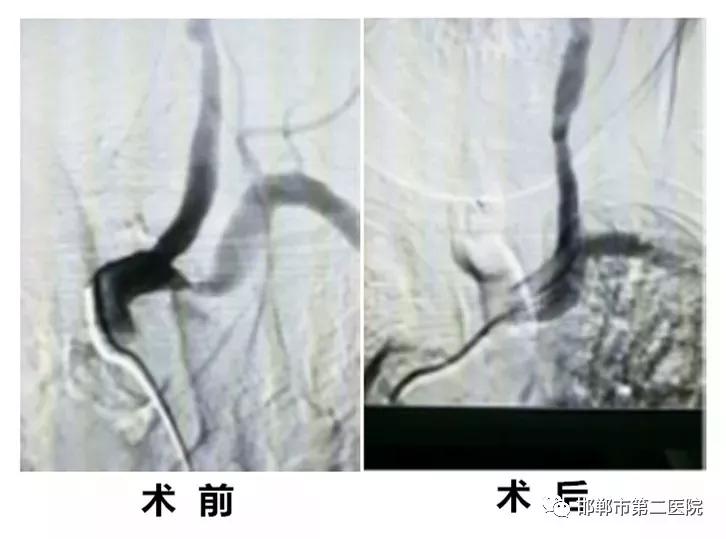

卫青祥主任看过病人后,明确患者反复晕厥并出现头晕症状为右侧锁骨下动脉重度狭窄所致,只要解决狭窄就解决了患者所有症状,随后血管造影证实右侧锁骨下动脉起始端局限性重度狭窄,狭窄率约80%,符合微创介入支架植入指证。

经精确定位微创介入植入支架后,再次造影支架完全覆盖狭窄段,贴壁良好,残余狭窄率约零,术后监测双侧血压基本一致并基本正常,手术十分成功。